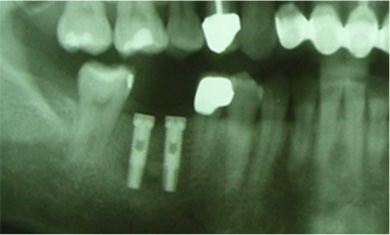

單顆雙植體 案例一